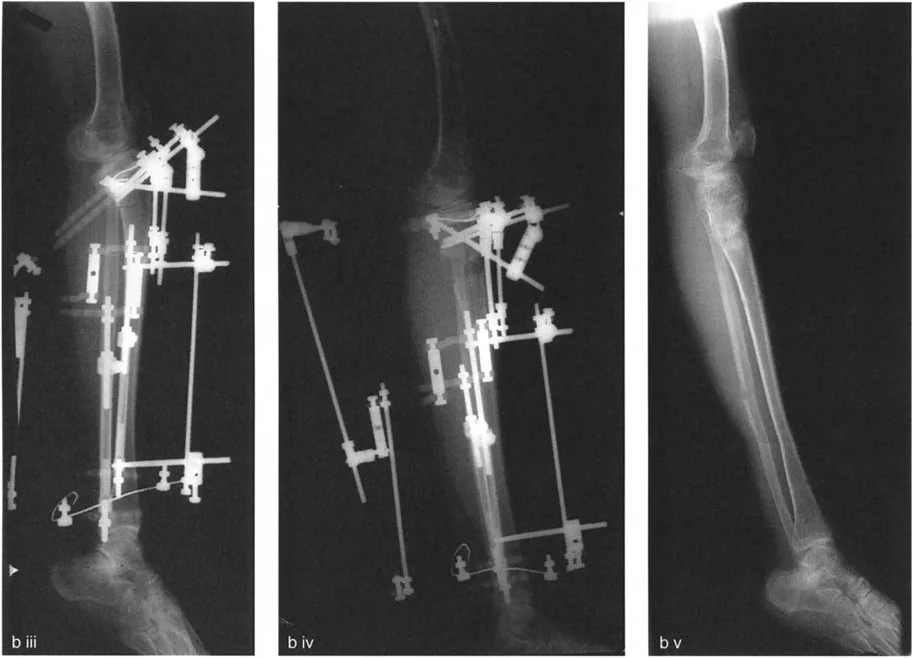

العلاج: جراحة إعادة تنظيم الركبة (Osteotomy)

تُعد جراحة إعادة تنظيم الركبة، أو قطع العظم التصحيحي (Osteotomy)، حلاً جراحيًا فعالًا لخشونة المفصل أحادي الحجرة وتشوهات الركبة. الهدف الرئيسي من هذا الإجراء هو إعادة توزيع الأحمال داخل المفصل، تخفيف الألم، وتحسين وظيفة الركبة، وقد يؤخر الحاجة إلى استبدال المفصل الكلي.

تتضمن جراحة قطع العظم قطع العظم (عادة عظم الفخذ أو الساق) وإعادة تشكيله لتغيير محاذاة المفصل. يمكن أن يكون القطع:

- قطع العظم بالوتد المفتوح (Opening Wedge Osteotomy): يتم عمل قطع في العظم ثم فتح فجوة صغيرة تُملأ غالبًا بطعم عظمي، مما يطيل الجزء المعني من العظم ويصحح المحاذاة.

- قطع العظم بالوتد المغلق (Closing Wedge Osteotomy): يتم إزالة جزء صغير من العظم على شكل وتد، ثم تُغلق الفجوة وتُثبت العظام، مما يقصر الجزء المعني ويصحح المحاذاة.

يتم تثبيت العظام بعد القطع باستخدام صفائح ومسامير أو تثبيت خارجي، لضمان التئام العظم في الوضعية الجديدة.

تصحيح تحدد حركة الركبة (Flexion Deformity - FFD)

- التصحيح التدريجي: في حالات تحدد الحركة الشديدة أو المعقدة، قد يكون التصحيح التدريجي باستخدام التثبيت الخارجي هو الخيار الأكثر أمانًا.

تصحيح الركبة الارتدادية (Recurvatum Deformity - Hyperextension)